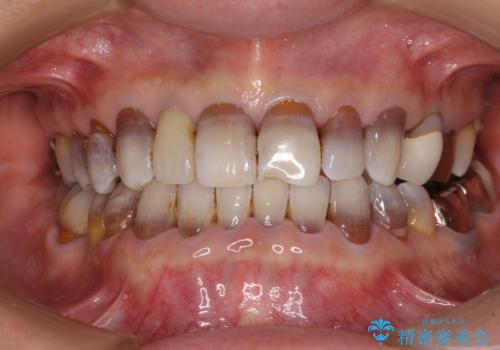

- 八重歯を気にして来院された患者様です。

本来であれば八重歯の隣後方の歯を抜歯するのですが、その後ろの歯が乳歯であり後続永久歯もなかったため、乳歯を抜去することとしました。

前から5番目の乳歯は、後続永久歯である小臼歯と比べて幅径が大きいため、移動に時間がかかりましたが、きれいに仕上げることができました。